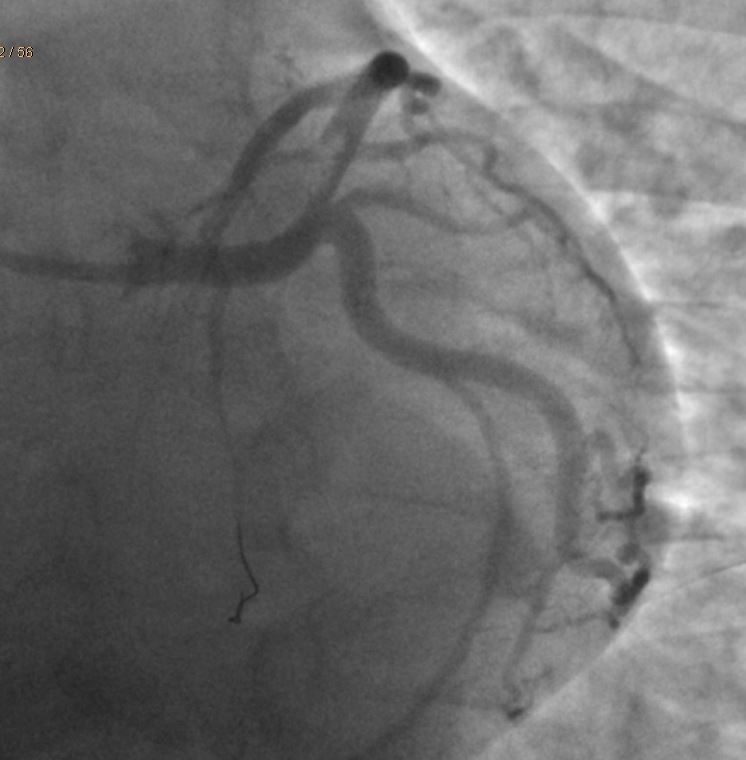

Case Presentation: A twenty-two-year-old male with no significant past medical history who presented with chest pain and found to have ST-segment elevation in leads II, III, aVF and V4-V6 leads. On subsequent EKG’s, patient had new ST-segment elevations in antero-lateral leads with dynamic changes. Cardiac catheterization showed acute dissection with thrombosis of the distal left main coronary artery leading into the ostial left anterior descending artery. Patient had no cardiac risk factors including hypertension, hyperlipidemia, diabetes or family history of early cardiac disease. On further inquiry, patient was found to be on two separate performance enhancing supplements which contained Synephrin, a sympathomimetic chemical which was later attributed as the cause of his acute coronary syndrome. Synephrin acts on alpha-1 adrenergic receptors causing peripheral and coronary vasoconstriction, hypertension and hyperglycemia. Increased hemodynamic stress on the coronary arteries can lead to fatal dissections. Ours is an atypical case of synephrin-induced non-atherosclerotic spontaneous coronary artery dissection which helps caution the physicians about the importance of dietary supplement use in the history and possible side-effects of such performance enhancing additives.

Discussion: This is an interesting case of a young active male with no apparent past medical or familial risk factors who presented with STEMI secondary to dissection with thrombosis of distal left main coronary artery extending to proximal LAD. The patient’s condition could be attributed to his use of synephrin containing weight-loss and performance-enhancing supplements. Administration of beta blockers pre-procedure might also have led to the unimpeded alpha action of the adrenergics in this case. Synephrin is a naturally occurring alkaloid which has been used in combination with caffeine in several weight-loss and dietary supplements. Pharmacologically synephrin has its action on alpha-1 adrenergic receptors causing effects such as peripheral vasoconstriction, hypertension and hyperglycemia. Unsupervised use of such supplements could be risky and even fatal. A definitive causal relation between the dietary supplement intake and coronary dissection cannot be drawn in this case; however, given the paucity of any other likely risk factors, the event is presumably secondary to the hypertension and sympathetic over -activity from synephrin.